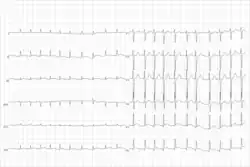

Telemetry strip of an asymptomatic sinus pause during COVID-19 pneumonia. | |

![]() | |